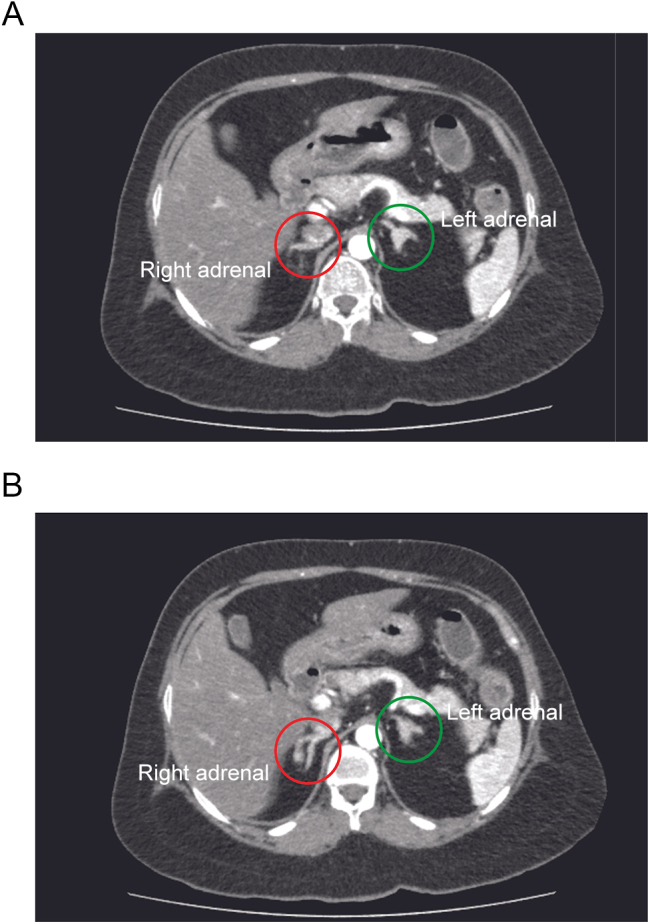

Summary: Cushing syndrome (CS) is an endocrine disorder with far-reaching complications that extend beyond the disease remission. Diagnosis of the aetiology of CS can be challenging, whether it is dependent or independent of adrenocorticotrophic hormone (ACTH). Here, we describe a case of ACTH-independent CS due to primary pigmented nodular adrenocortical disease (PPNAD) in a 33-year-old female patient with several complications of CS, including diabetes, hypertension, osteoporosis and severe depression with suicidal ideation. In this case, following the demonstration of ACTH independence of CS, it was challenging to localise the lesion as there were bilateral adrenal lesions. Furthermore, preoperative efforts in localisation in the form of adrenal venous sampling (AVS) failed. However, the diagnosis of PPNAD was confirmed using an intraoperative frozen section and macroscopy, and the patient underwent bilateral adrenalectomy during the same surgery. This case highlights a novel approach to diagnosing and managing PPNAD intraoperatively in a resource-limited setting where preoperative localisation studies have failed.

Learning points: AVS can assist in localising the functional lesion in ACTH-independent CS due to bilateral adrenal lesions. PPNAD diagnosis can be made through a frozen section intraoperatively, thus giving further confirmation needed to justify bilateral adrenalectomy in such cases.